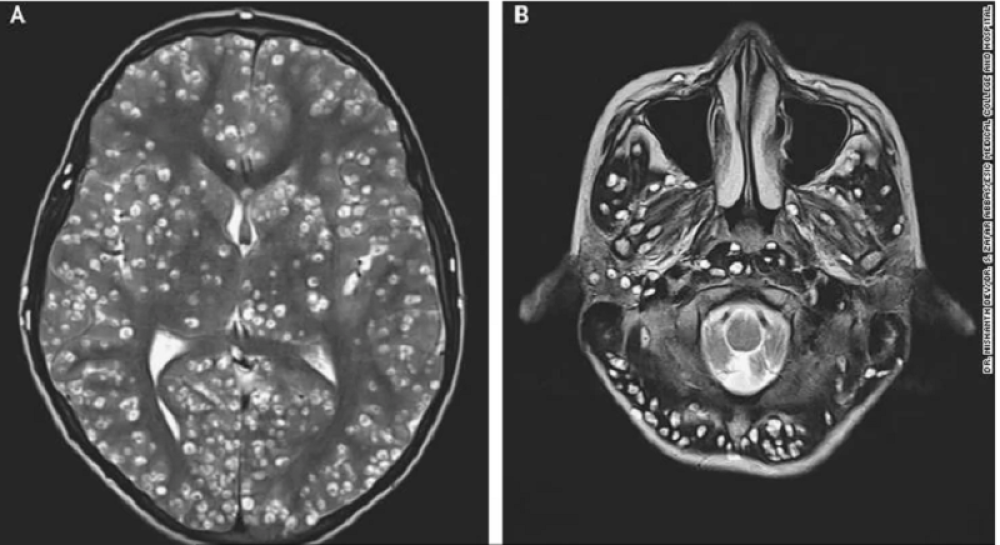

Tema: paraziti